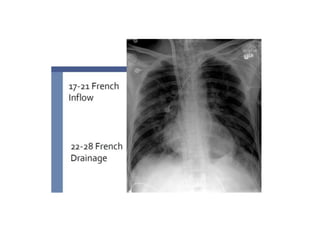

DUAL LUMEN

CATHETER

Single cannula

Fluoroscopy, ECHO (TEE)

Low recirculation

Facilitate mobility

Less sedation